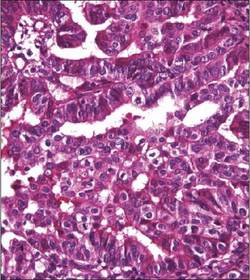

Adenocarcinoma de Endométrio Grau II.

Adenocarcinoma de endométrio grau III.

Descreva os estágios de classificação do adenocarcinoma de endométrio. Grau I - Predomínio de Glândulas (bem diferenciado). Grau II - Glândulas em proporção semelhante à área sólida (moderadamente diferenciado). Grau III - Há predomínio de áreas sólidas (cels epiteliais proliferadas), (pouco diferenciado).